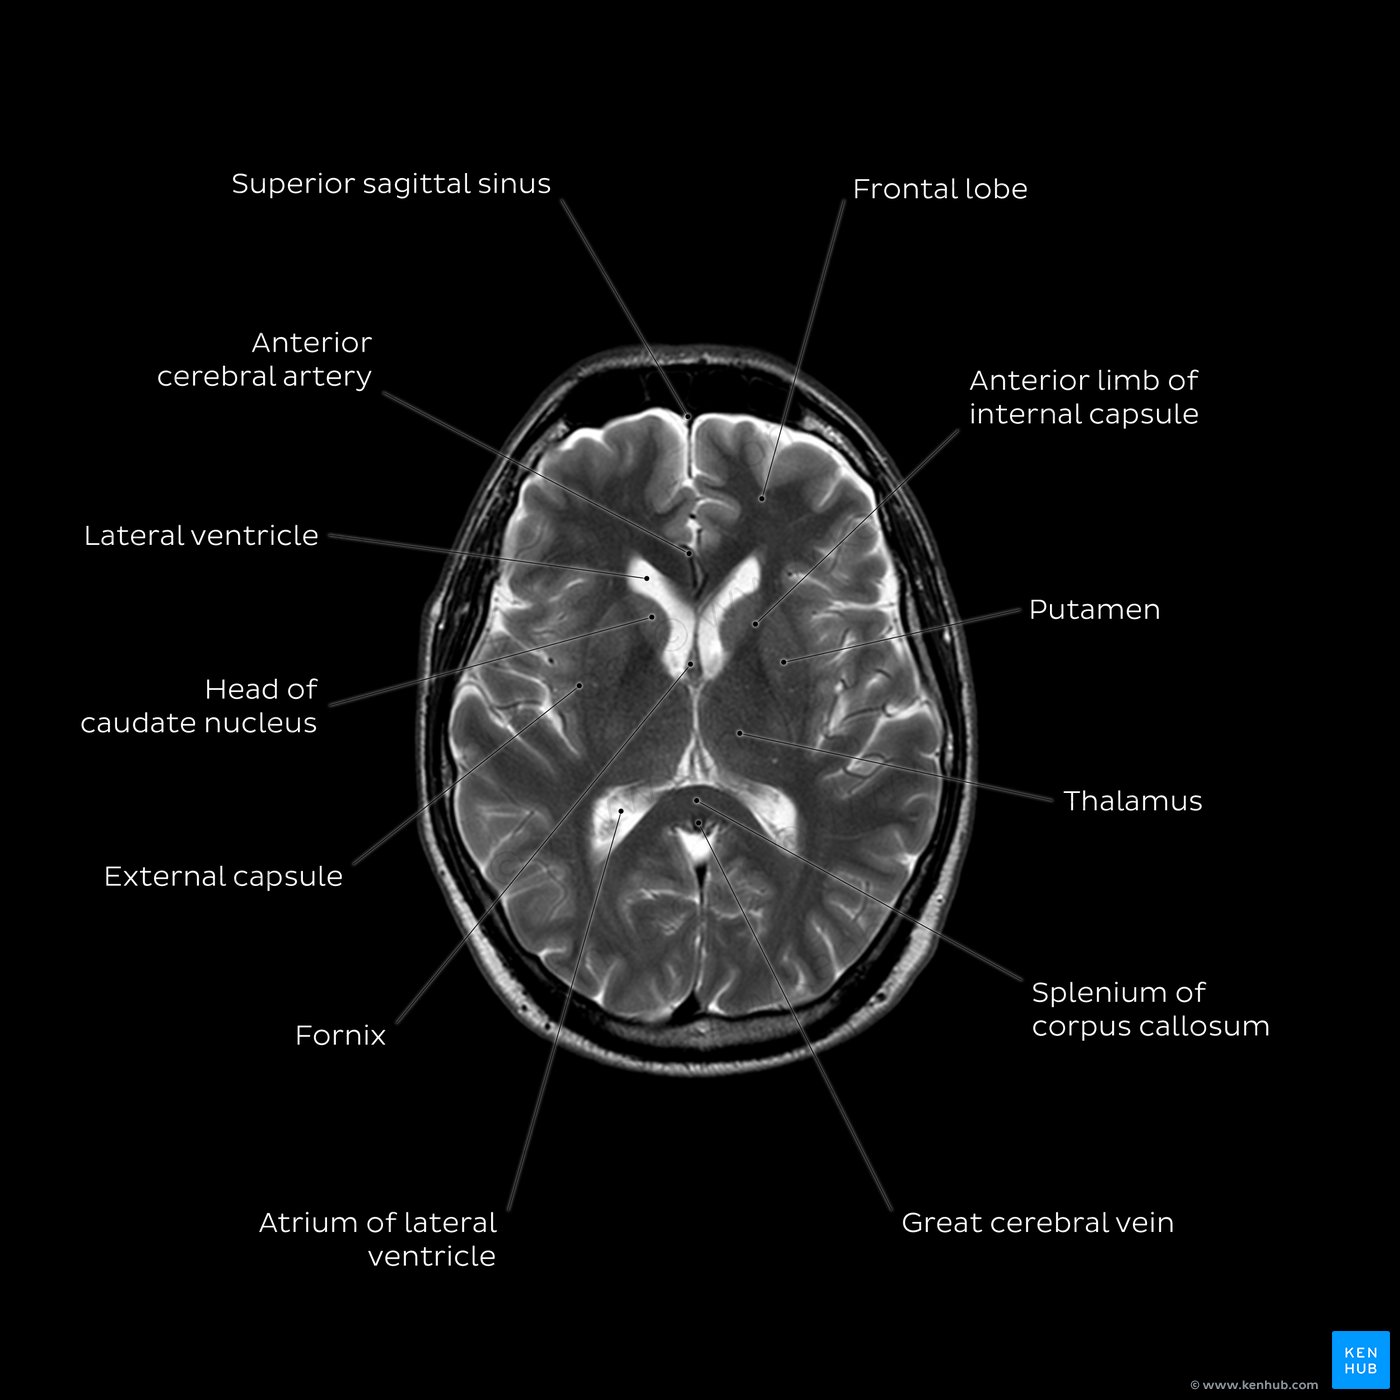

Curious about the average womb size? Discover what is considered normal for uterine dimensions, how age and pregnancy history affect it, and when changes in size might indicate underlying health concerns. Learn the clinical facts about reproductive anatomy and uterine health in this informative guide designed to help you better understand your body’s unique physiological measurements.